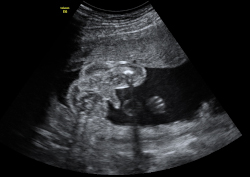

Ecografía Embarazo 4D - SEMANA 20